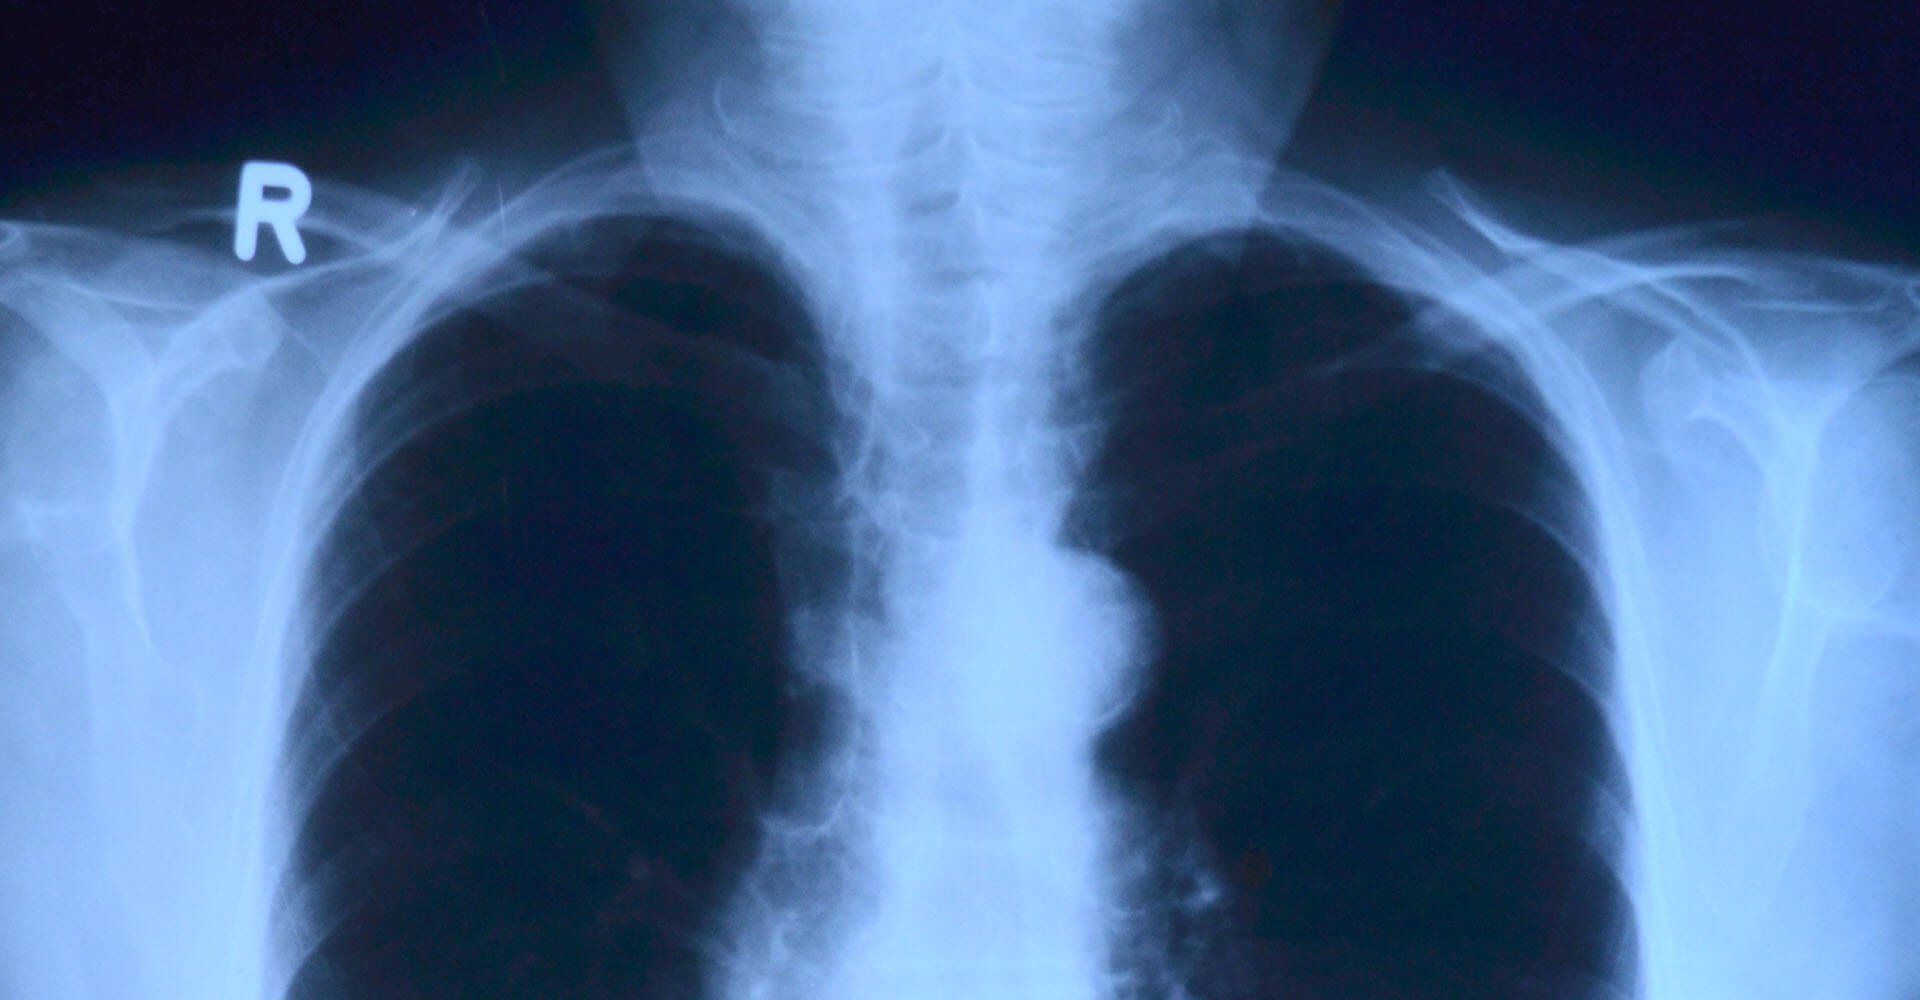

Затемнения легких при поражении туберкулезом, фиброзы, склерозы, новообразования, кисты, абсцессы, и даже присутствие посторонних газов — все это может быть выявлено на флюорографии. Изначально этот анализ стал востребован именно в связи с профилактикой туберкулеза, с которым легко справиться, вовремя его выявив, и почти невозможно – запустив.

Существуют также обследования, которые определяются не как флюорография, а именно как рентген легких – их мощность выше, как и качество снимка. Однако проходить такое обследование без специального назначения незачем – оно существует не для плановой профилактики, а скорее для выявления сложных патологий легкого и грудной клетки.